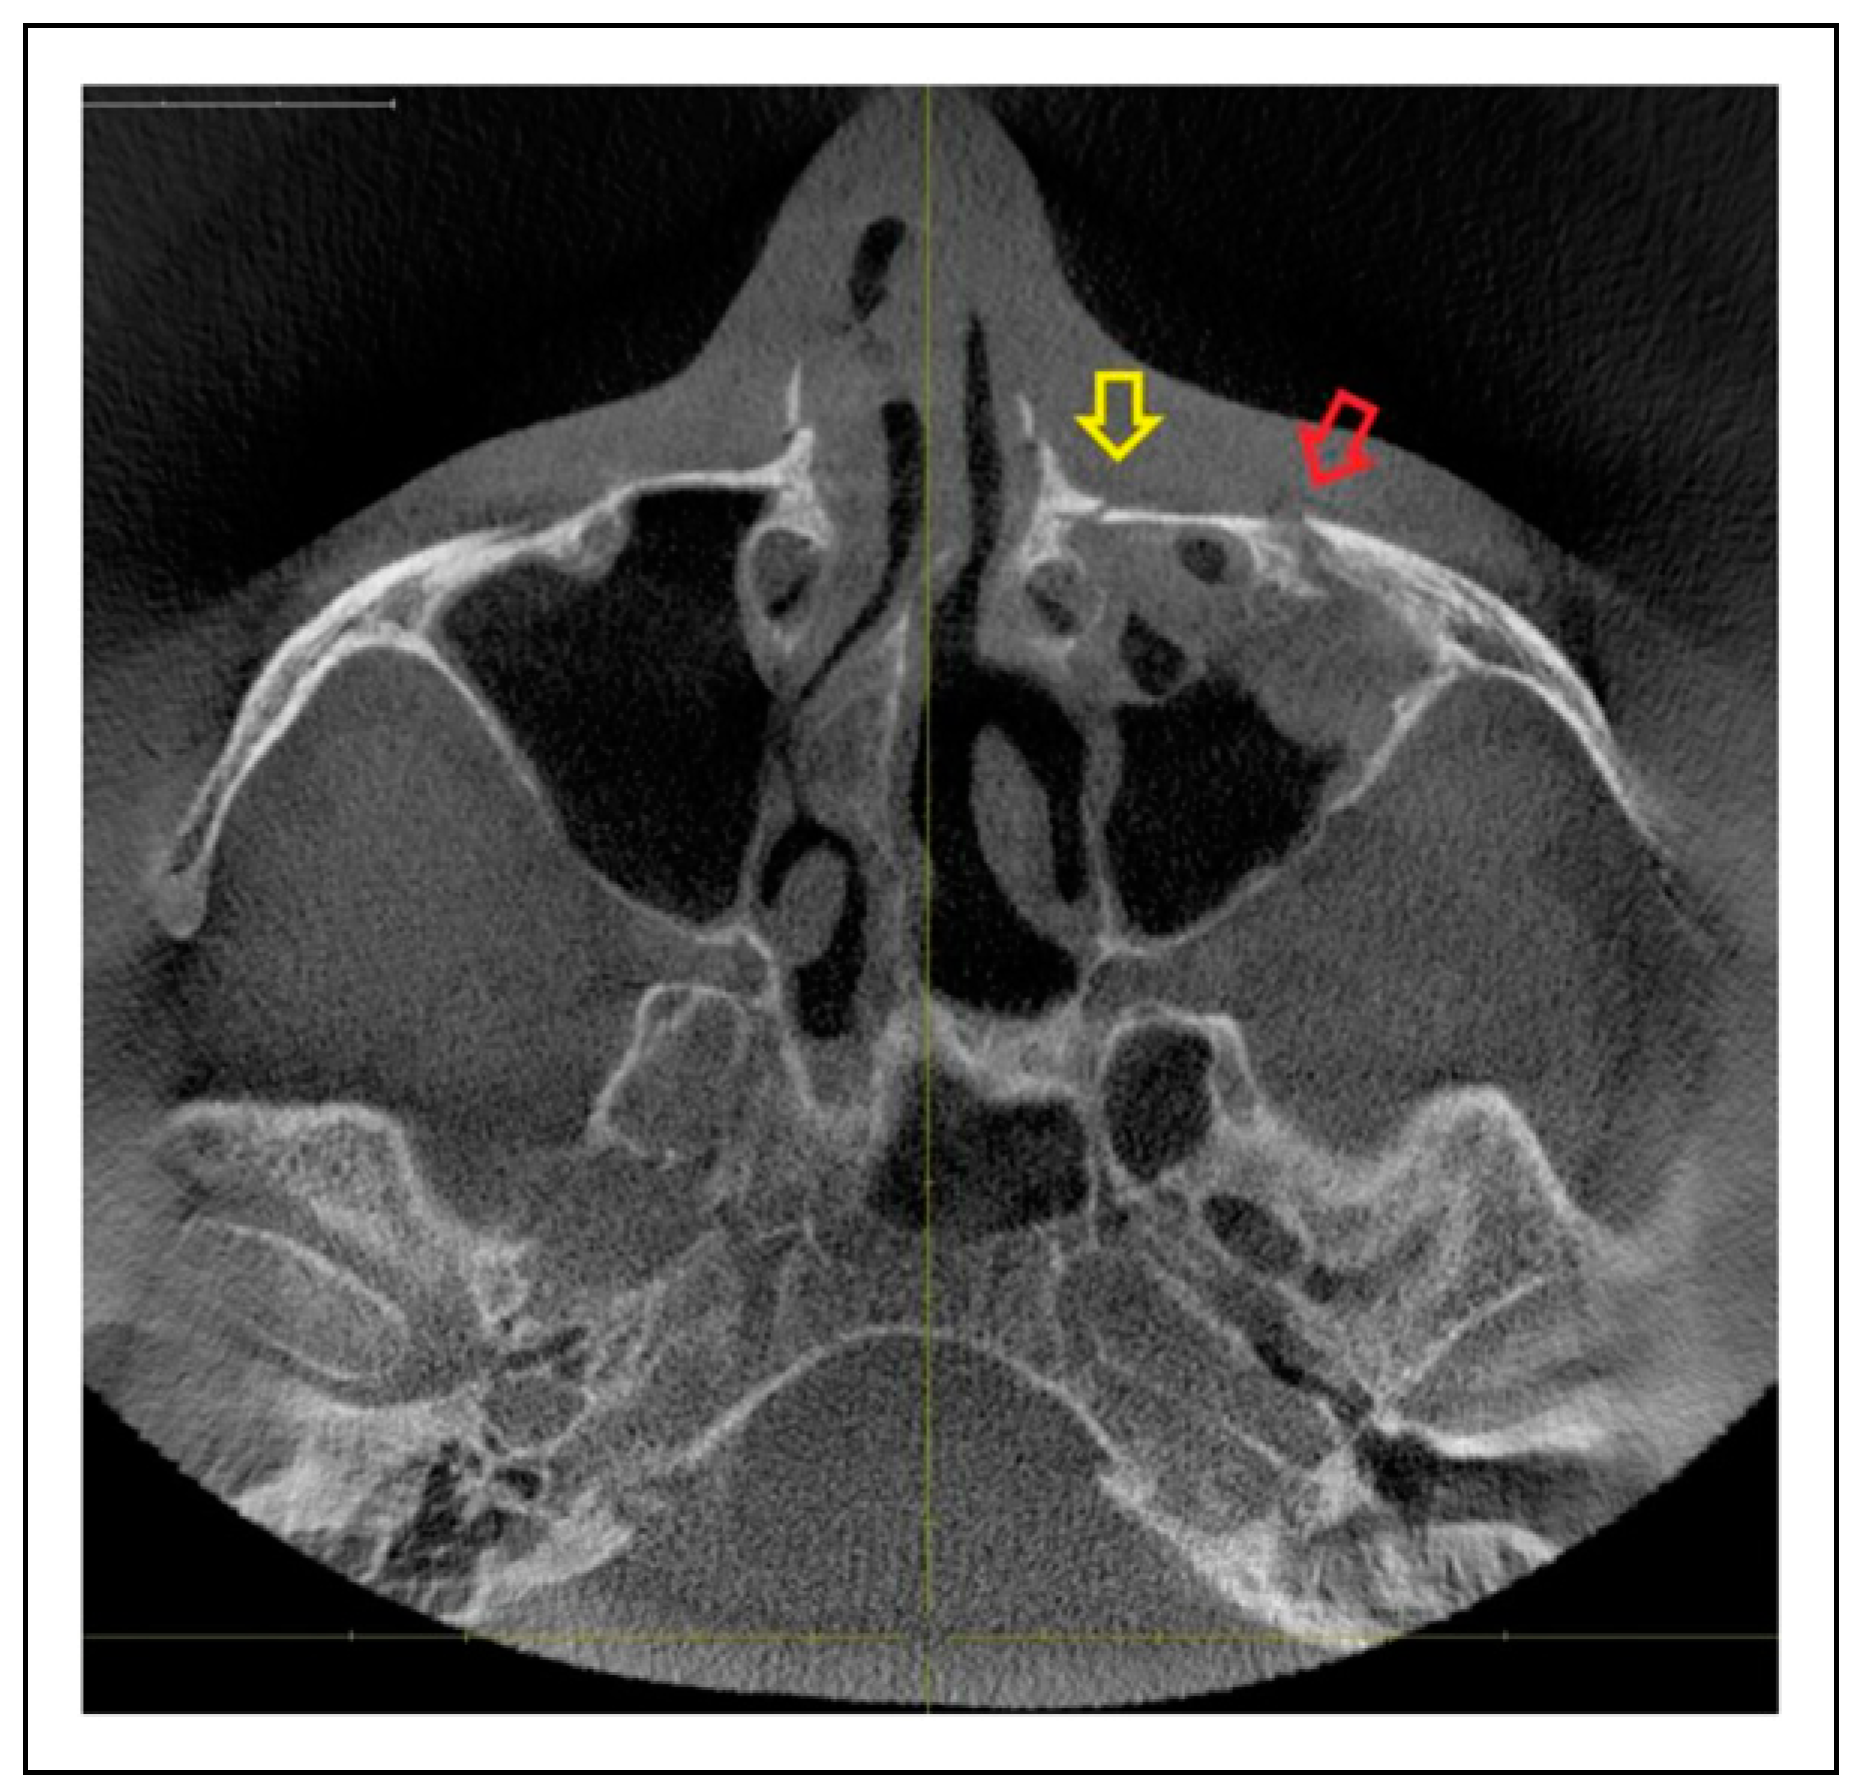

- Fracture location according to the anatomic sutures of the zygoma

- Radiologic involvement of maxillary sinus wall and paranasal buttress fractures.

- Zygomaticosphenoidal suture (ZS)—the anterolateral orbital floor

- Bisutural fracture with the following fracture line combinations:

- Trisutural fracture with the following fracture line combinations:

- IOR + ZF suture + ZS suture

Patterns of ZMO Fractures Regarding the Anatomic Sutures of the Zygoma

Fracture Prevalence of Maxillary Sinus Wall and Paranasal Buttress as Concomitance to the ZMO